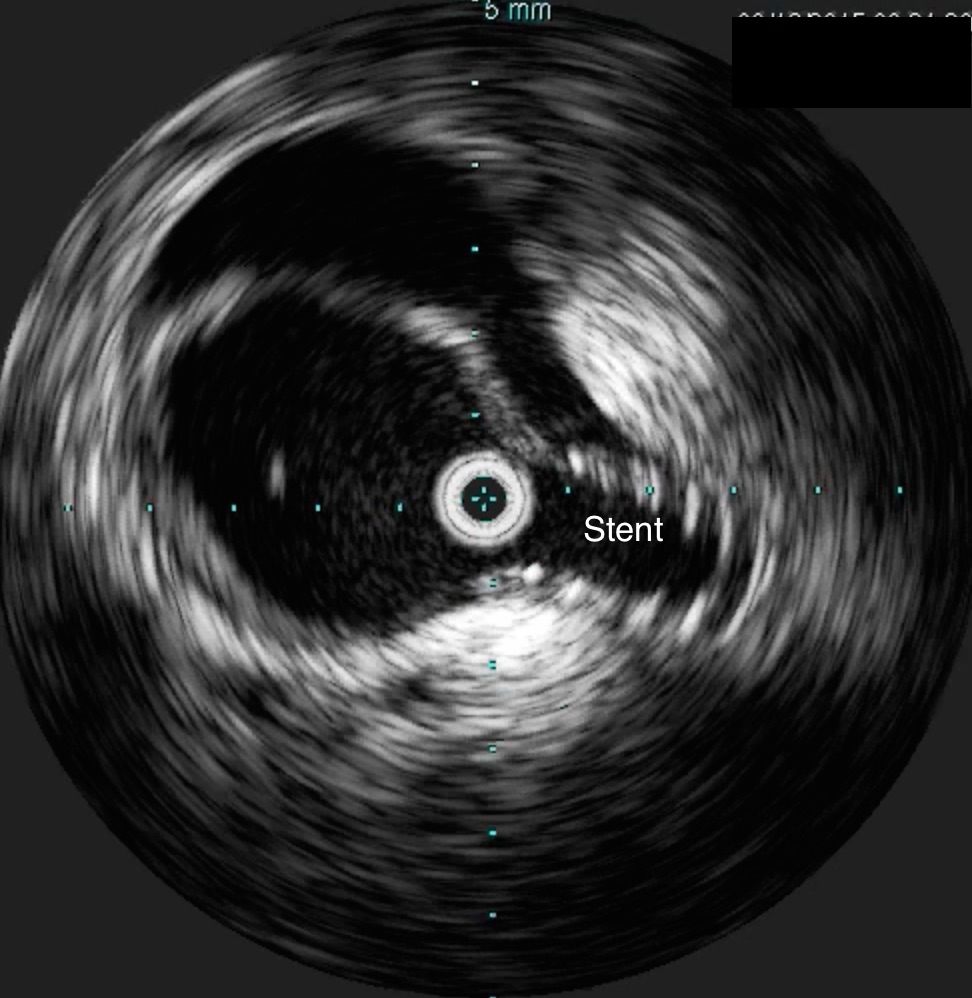

He was taken to the hybrid operating room. Right groin access was achieved and wire access to the arch was achieved. IVUS (Intravascular ultrasound, Volcano) was used to confirm the location of the wire -I believe this is an important adjunct as simply passing the wire doesn’t guarantee travel up the true lumen.

The SMA completely filled as did the celiac axis and both renal arteries. I opted not to treat the right renal artery as we had given 250mL of contrast, and it was filling well without intervention. The patient was making excellent urine and his blood pressure had been maintained with mean arterial pressures above 70mmHg. At this point, IVUS confirmed good deployment of the stent.